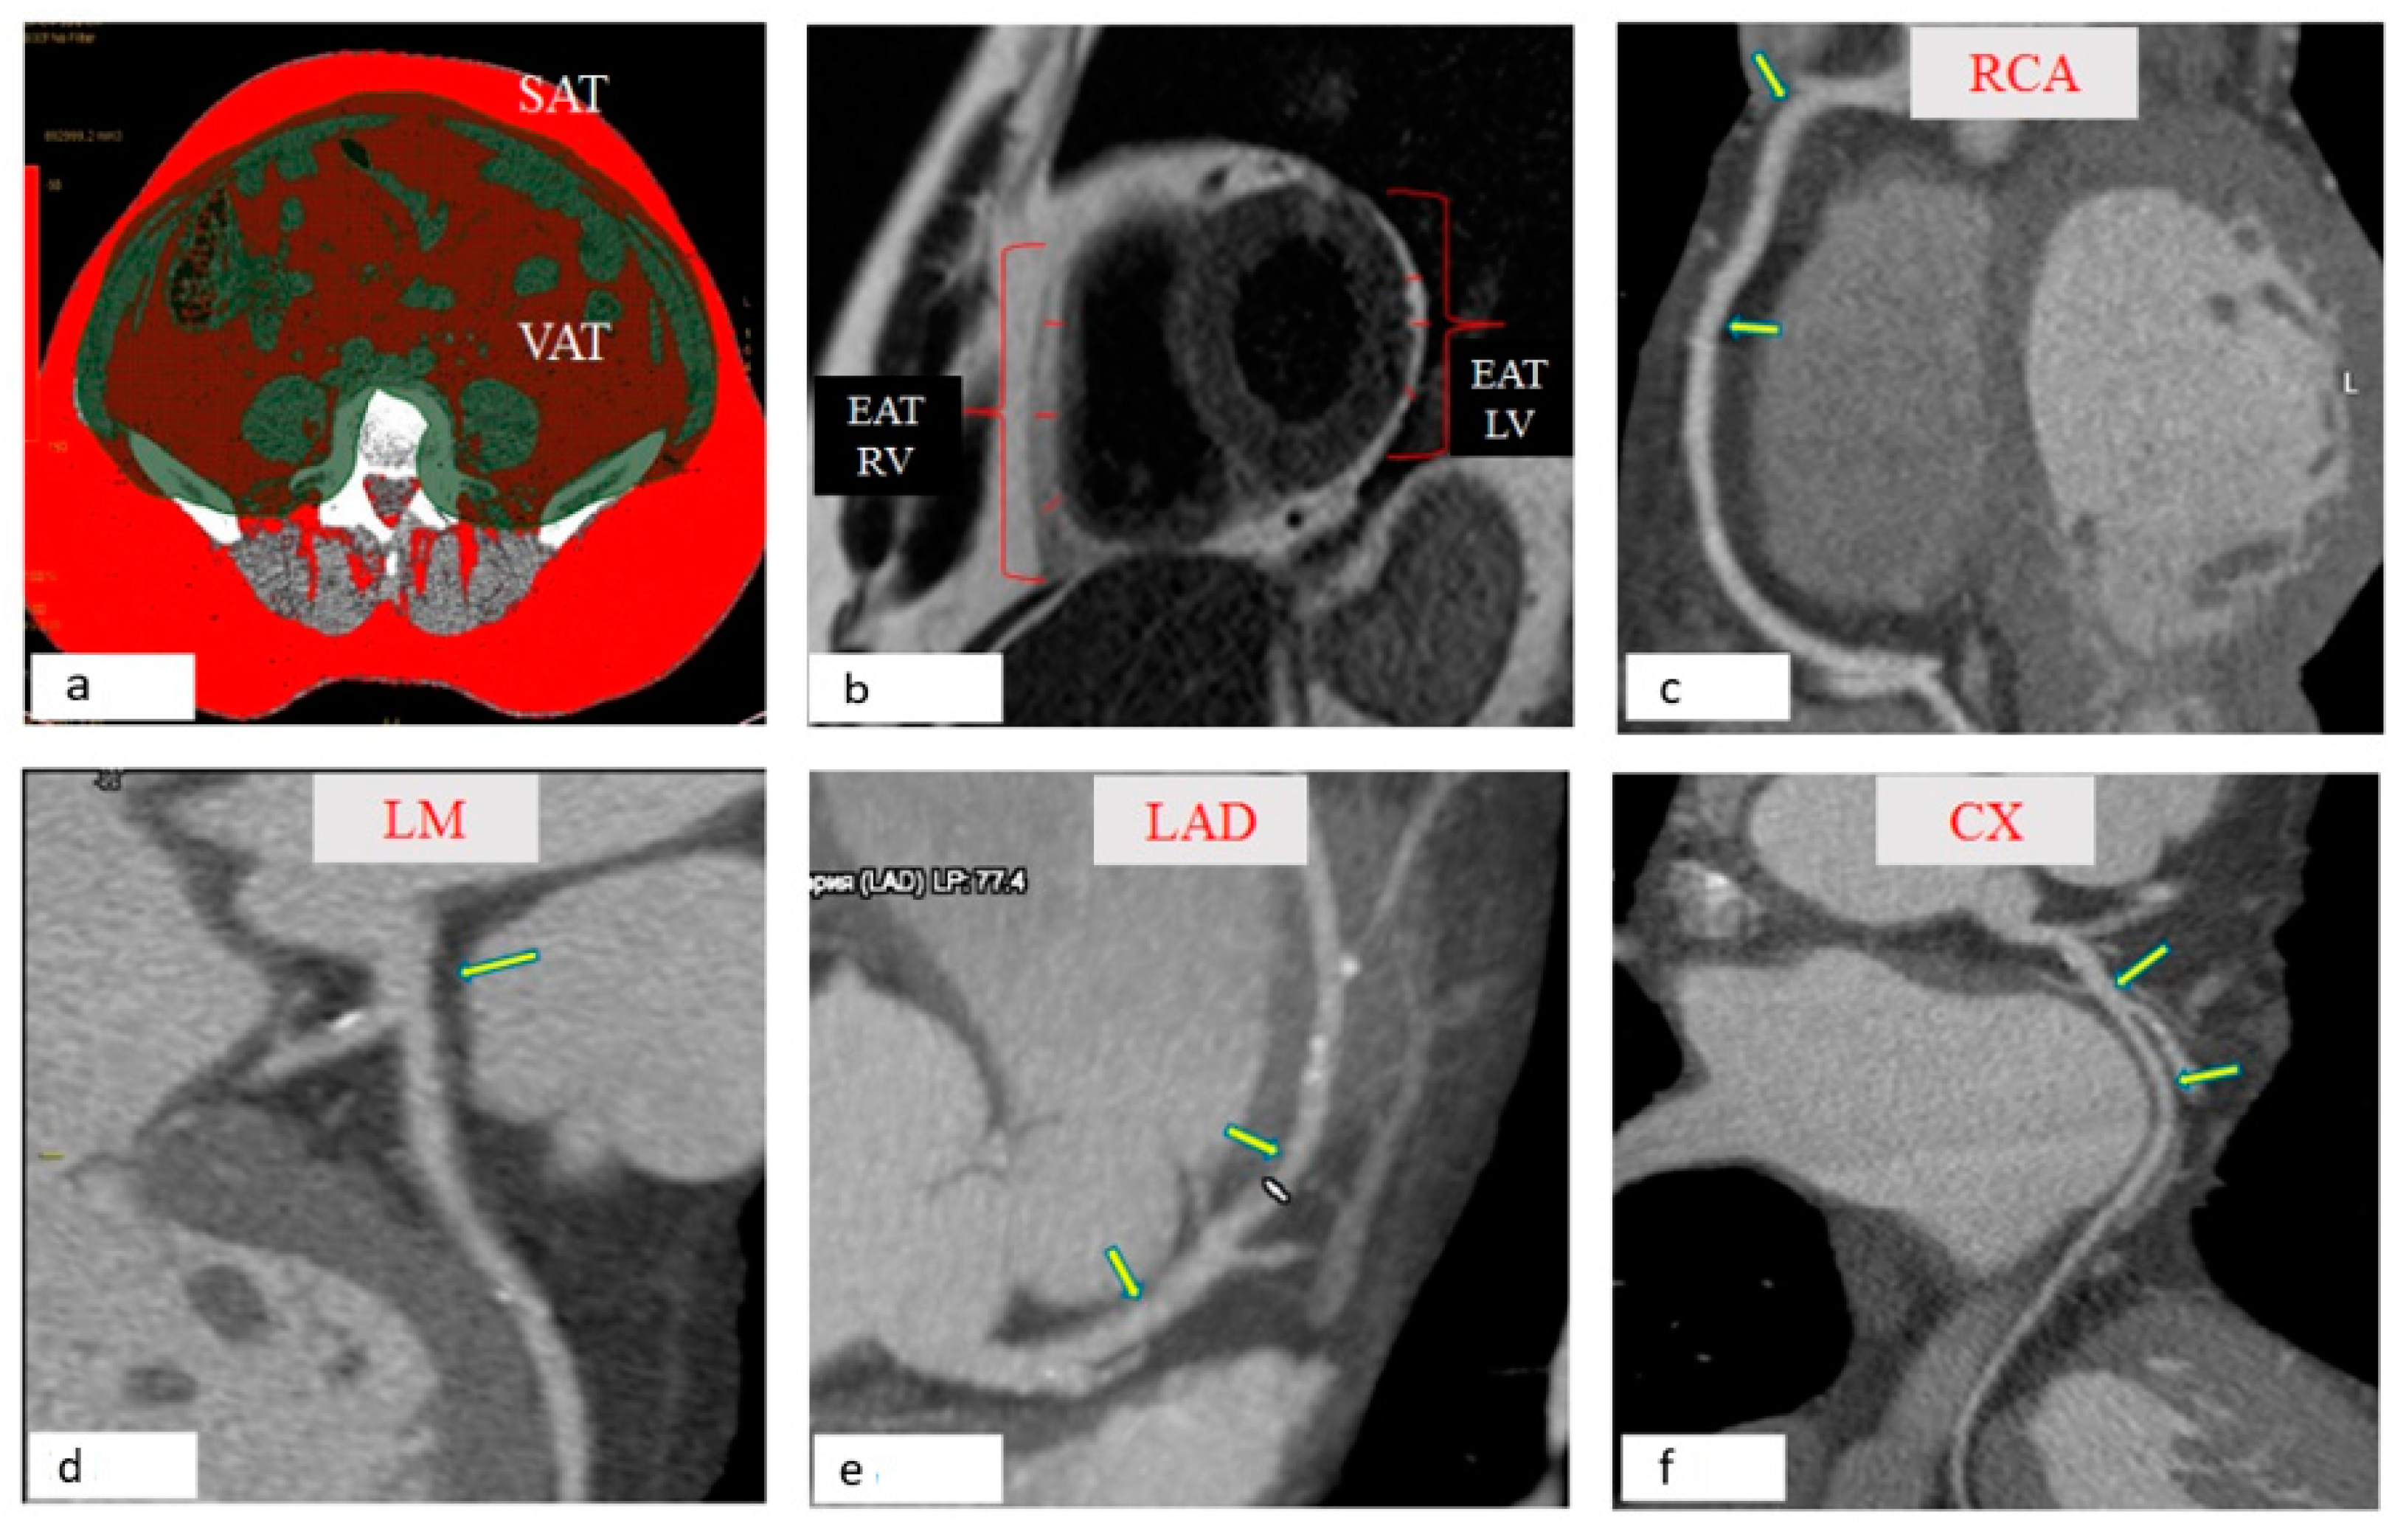

2.3. Measurement of the Area of SAT, EAT, and PVAT

3.1. Visualization of Local Fat Depots (Epicardial, Perivascular, Abdominal) in Patients with Coronary Heart Disease